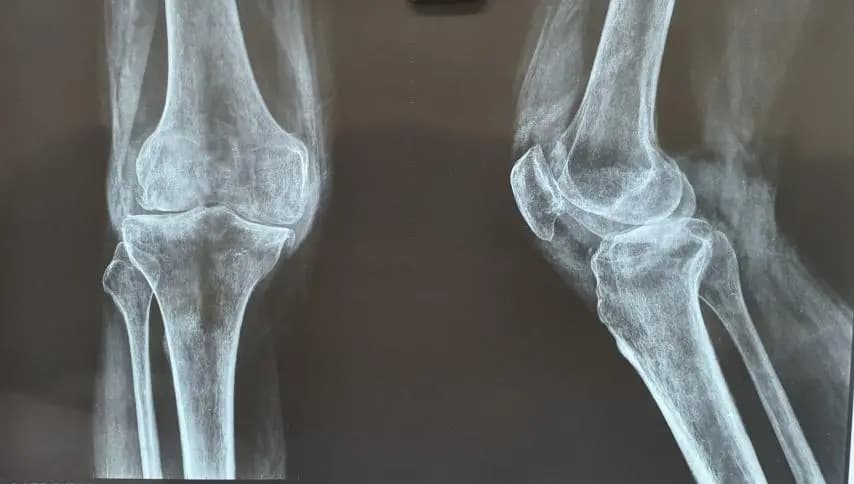

Which scan is right: X-ray, MRI, or CT?

X-Ray

Best for: Bones

Cost: Low

Knee: injury with swelling, locking, or suspected ligament damage. Shoulder: loss of motion after injury or suspected rotator cuff problems. Spine: persistent nerve symptoms or weakness that needs clarification (see Spine & Nerve Pain Care). Hip: deep groin pain with stiffness or suspected joint pathology that needs clarification. Fracture: confirming stability and tracking healing (see Fracture & Trauma Care).